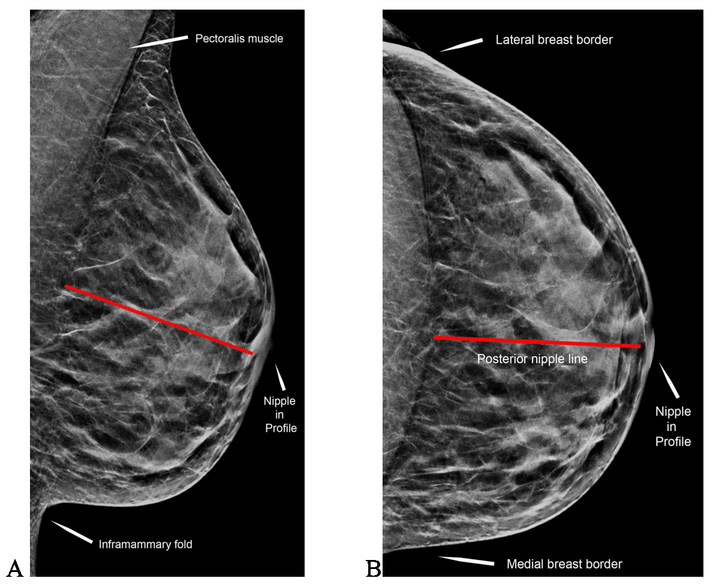

For adequacy the posterior nipple line has to be within what distance of each other on CC and MLO?

1 cm

nipple is required to be in profile on how many views?

at least one view

The pectoralis muscle should extend to at least within ________ cm of the posterior nipple line

Using ACR accrediation criteria for clinical image evaluation, what is recommended for visualization of the pectoralis muscle on mammorgraphy?

extends to the level of the posterior nipple line